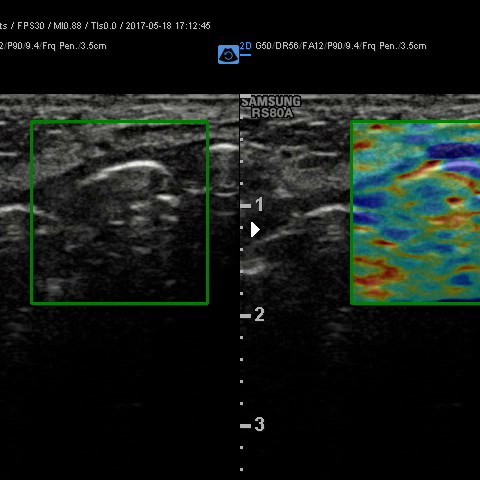

Elastografia.

To przełomowa metoda diagnostyczna wykorzystującą fakt, że chora tkanka zmienia swoją twardość. Można powiedzieć, że elastografia jest cyfrowym rozwinięciem badania dotykiem, kiedy lekarz ocenia twardość i spoistość badanego narządu.

Elastografię proponujemy przede wszystkim w przypadkach:

• podejrzanych zmian w tarczycy

• podejrzanych zmian w piersiach

• zmian miąższowych wątroby

• oceny włóknienia wątroby (choroby wirusowe, marskość)

• ocena stłuszczenia wątroby

• diagnostyka NADCIŚNIENIA WROTNEGO - badanie śledziony

W wielu przypadkach elastografia pozwala uniknąć biopsji i rozwiać wątpliwości co do łagodnego, lub złośliwego charakteru zmiany.

Badanie elastograficzne można wykonać w naszej pracowni jako rozszerzenie badania USG tarczycy i piersi (ocena guzków), a także jako samodzielne badanie – elastografia wątroby w celu oceny włóknienia(stosowana u nas metoda elastrografii 2D-SWE jest znacznie dokładniejsza od dotychczas stosowanej metody TE [FIBROSCAN®].